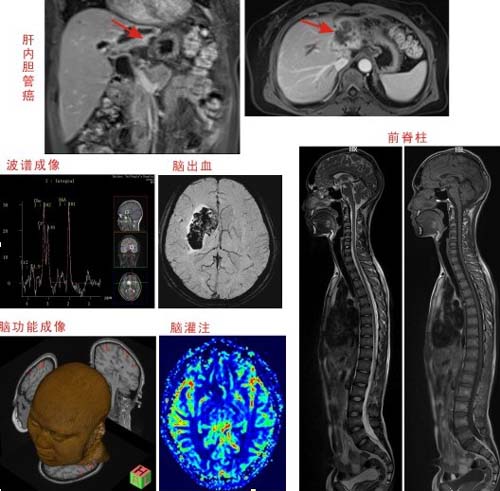

我院引进的西门子MAGNETOM Essenza 1.5特斯拉超导磁共振机,是西门子1.5T核磁共振新一代高性能的高场强,该机型功能齐全,图像清晰,信噪比好而且配有磁共振革命性技术——全景成像技术。采用人性化设计,配置强劲的梯度系统,具有操作智能化、扫描高速化和应用创新化等三大特点。用于常规核磁共振成像、水成像、血管成像、弥散、磁敏感成像和波谱成像等功能,对人体无伤害、无不适感,并可重复检查,是新时代高科技影像医学检查的发展趋势。

与早期传统磁共振相比,扫描视野更大、扫描速度更快、图像对比度更清晰,能对人体各个部位进行多序列的扫描检查,并可显示任意方位的图像,能开展多项诊疗工作。可应用于全身各部位的常规检查,特别是对脑、脊髓、骨关节软组织神经、血管和体部脏器的检查有独到之处。该设备投入使用后,将为神经内科、神经外科、普外科、泌尿外科、骨科、心血管内科、肿瘤科等科室患者提供无辐射、无创伤的影像检查,医生能够从其高质量的图片清楚地看到许多以前无法看清的细小病灶,发现以前无法发现的疾病,为疾病的准确定性提供了保证,对临床具有极高的指导价值。

该机适用于全身各系统不同疾病的检查,如肿瘤、感染、创伤、退行性病变及各种先天性疾病的检查。对人体无损伤、无射线损害,无骨性伪影,高分辨率,图像清晰,不需要使用对比剂即可显示血管结构。

该机可进行神经系统、心血管系统、骨关节系统等全身各个系统的不同疾病的检查,对血管梗塞、血管瘤、动脉夹层、血管畸形、胆道以及泌尿系结石、肿瘤、梗阻的诊断具有极大的临床价值,可发现CT无法发现的超早期脑梗塞病变,为挽救患者生命和改善预后、减少致残率赢得时间。